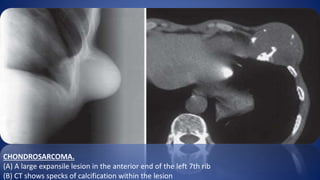

CHONDROSARCOMA.

(A) A large expansile lesion in the anterior end of the left 7th rib

(B) CT shows specks of calcification within the lesion